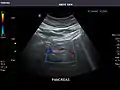

Aorta

Aorta: Visualized portions normal in caliber, 16 x 15 mm.